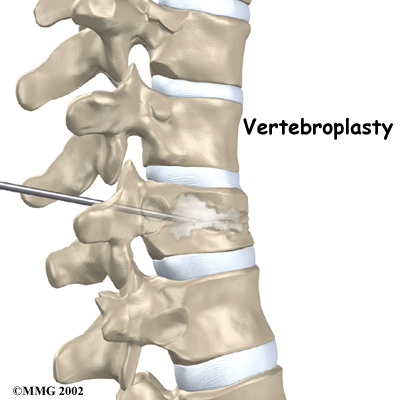

Vertebroplasty

This procedure is most helpful for reducing pain. It also strengthens the fractured bone, enabling patients to rehabilitate faster.

To perform vertebroplasty, the surgeon uses a fluoroscope to guide a needle into the fractured vertebral body. A fluoroscope is a special X-ray television that allows the surgeon to see your spine and the needle as it moves. Once the surgeon is sure the needle is in the right place, bone cement, called polymethylmethacrylate (PMMA), is injected through the needle into the fractured vertebra. A reaction in the cement causes it to harden within 15 minutes. This fixes the bone so that it does not collapse any further as it heals. More than 80 percent of patients get immediate pain relief with this procedure.

Iron City Physical Therapy's Guide to Vertebroplasty